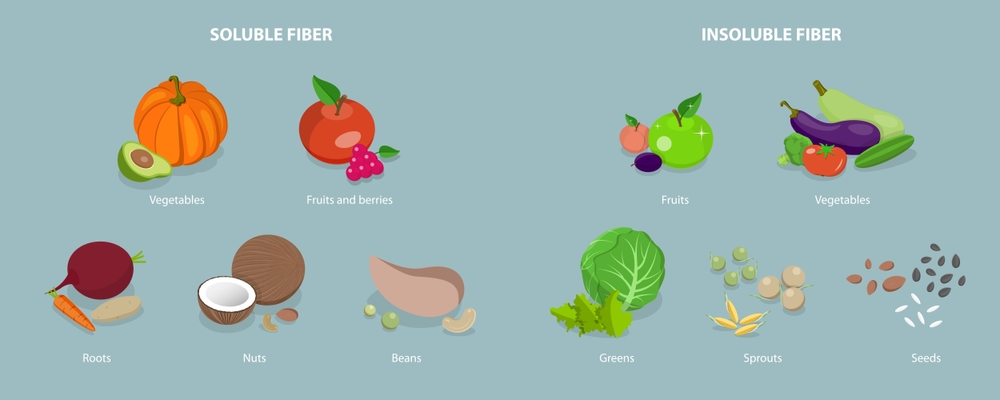

۱. افزایش مصرف فیبر غذایی

مصرف منابع فیبر محلول و نامحلول باعث افزایش حجم مدفوع و تسهیل حرکت آن در روده میشود. مواد غذایی غنی از فیبر عبارتاند از:

- سبزیجات برگدار (مانند اسفناج و کاهو)

- میوهها با پوست (مانند سیب، گلابی، آلو خشک)

- غلات سبوسدار (جو دوسر، نان کامل، برنج قهوهای)

۲. مصرف منظم فیبرهای غذایی

فیبرها نقش حیاتی در بهبود حرکات روده و پیشگیری از خشکی مزاج دارند. منابع غنی از فیبر شامل میوهها، سبزیجات، غلات کامل، حبوبات و دانههای خوراکی مانند تخمچیا و بذر کتان هستند. ترکیب فیبرهای محلول و نامحلول در رژیم غذایی بهترین تاثیر را دارد.